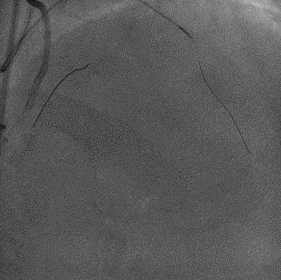

PCI过程

双侧造影,RCA 7F AL1.0,Runthrough导丝置于远端。

LCA 7F XB3.5,Cosair135,尝试Pilot200失败,进入假腔,Judo3成功通过闭塞段,换入Pilot150后,仍然进入假腔,再次使用Judo导丝,进入前降支远端,微导管造影,证实为真腔内,送入工作导丝。

Tip injection确认真腔,更换runthrough,2.0*20mm球囊预扩。

IVUS提示LAD近中段弥漫钙化,接近270度,钙化长度约26mm

LAD Stent 2.5*36mm,3.0*29mm ;Immediate image ,TIMI3

继续开通LCX,Pilot200 成功通过闭塞段,Tip injection 确认真腔

更换runthrough,Ballon dilatation 2.0*20mm,2.75*15mm

LCX Stent 2.5*36mm, Immediate image ,TIMI3

IVUS LCX-LM,RUN2

支架膨胀、贴壁良好,LCX开口MSA 5.68mm²,LM MLA 5.67mm²。

NC 3.0*15mm,3.5*15mm后扩张;LM stent 4.0*19mm

Runthrough 掏LCX支架网眼,退LAD导丝,送入 NC 3.5*15mm扩张,优化开口支架形态

IVUS LAD-LM,RUN3,LAD口部MSA 9.03mm²,LM MSA 10.18mm²

NC Ballon dilatation 3.0*15mm,3.5*15mm,4.0*12mm

Final result